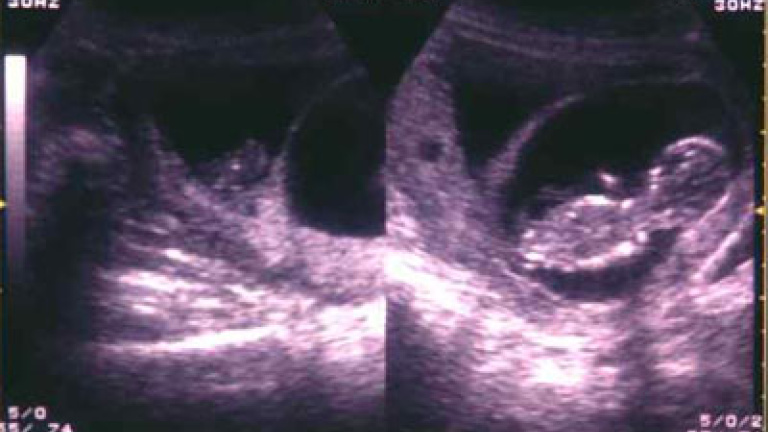

La mujer, Julia Grovenburg, descubrió la situación durante una ecografía a la que se sometió a las ocho semanas de embarazo y que mostró a dos bebés separados por dos semanas y media, uno claramente más desarrollado que el otro, ante lo que los doctores apuntaron la posibilidad de que se tratara de un caso de superfetacón.